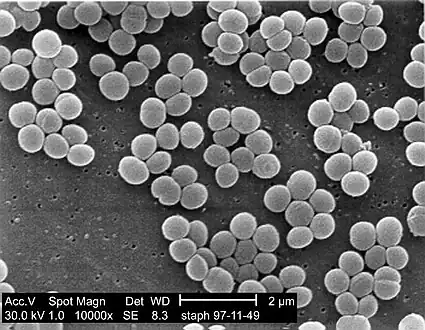

| SEM micrograph of S. aureus colonies; the grape-like clustering is common to Staphylococcus species. | |

A staphylococcal infection or staph infection is an infection caused by members of the Staphylococcus genus of bacteria. These bacteria commonly inhabit the skin and nose where they are innocuous, but may enter the body through cuts or abrasions which may be nearly invisible. Once inside the body, the bacteria may spread to a number of body systems and organs, including the heart, where the toxins produced by the bacteria may cause cardiac arrest. Once the bacterium has been identified as the cause of the illness, treatment is often in the form of antibiotics and, where possible, drainage of the infected area. However, many strains of this bacterium have become antibiotic resistant; for those suffering these kinds of infection, the body's own immune system is the only defense against the disease. If that system is weakened or compromised, the disease may progress rapidly.[1] Anyone can contract Staph, but pregnant women, children, and people with chronic diseases or who are immuno-deficient are often more susceptible to contracting an infection.[2]

The generic name Staphylococcus is derived from the Greek word "staphyle", meaning bunch of grapes, and "kokkos", meaning granule. [39]

The bacteria, when seen under a microscope, appear like a branch of grapes[40]